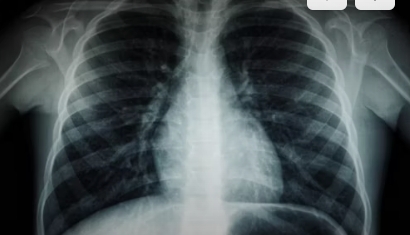

폐결절의 위험 인자는 흡연, 미세먼지 노출, 환경적 요인, 가족력 등이 있으며, 흡연자는 특히 주의가 필요합니다. 저선량 흉부 CT 검사는 폐암 조기 발견율을 기존 X-선 대비 7배 이상 높이는 것으로 알려져 있어, 고위험군에게 매우 중요한 검진 방법입니다.

폐결절이 발견되면 우선 CT 검사를 통해 크기, 모양, 경계, 내부 구조를 확인합니다. 미국의 가이드라인과 우리나라에서 변형해 적용하는 Lung-RADS 기준에 따르면, 결절의 크기와 성격에 따라 추적검사 간격과 추가 검사의 필요성이 달라집니다. 예를 들어, 6mm 이하의 고형 결절은 12개월 후 추적 검사를 권장하며, 8mm 이상의 결절은 조직검사나 PET-CT와 같은 정밀 검사가 필요합니다.